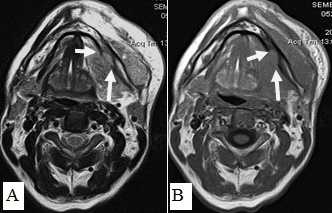

При МРТ-исследованиях оценка инфильтрации костной ткани проводилась по следующим показателям: отсутствие типичного гипоинтенсивного сигнала от кортикального слоя на Т1-ВИ и Т2-ВИ, появление сигнала высокой или средней интенсивности на Т1-ВИ и Т2-ВИ, соответствующего опухолевой ткани, появление гипоинтенсивного сигнала на Т1, гиперинтенсивного сигнала на Т2 или Т2 с подавлением сигнала от жировой ткани, что демонстрировало поражение костного мозга (рис. 15).

Рис. 15. Пациент С.,52 г. МРТ полости рта в аксиальной проекции в режиме Т2-ВИ (А) и Т1-ВИ (В). Рак дна полости рта с распространением на нижнюю челюсть, инфильтрацией мягких тканей щечной, подбородочной области слева. Выявляется деструкция кортикального слоя нижней челюсти слева, поражение костного мозга (стрелки)